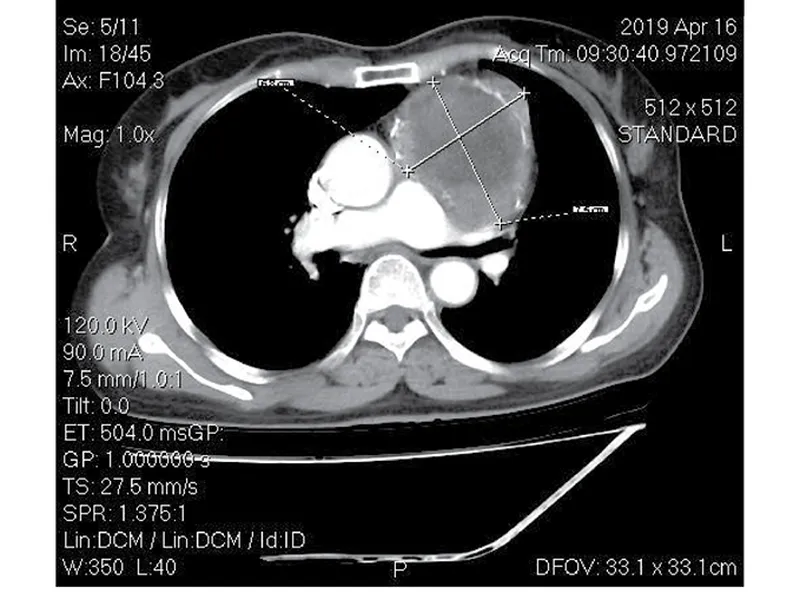

Sau đó bệnh nhân được chuyển lên bệnh viện Từ Dũ chụp MRI với kết quả tương đồng tại bệnh viện chúng tôi.